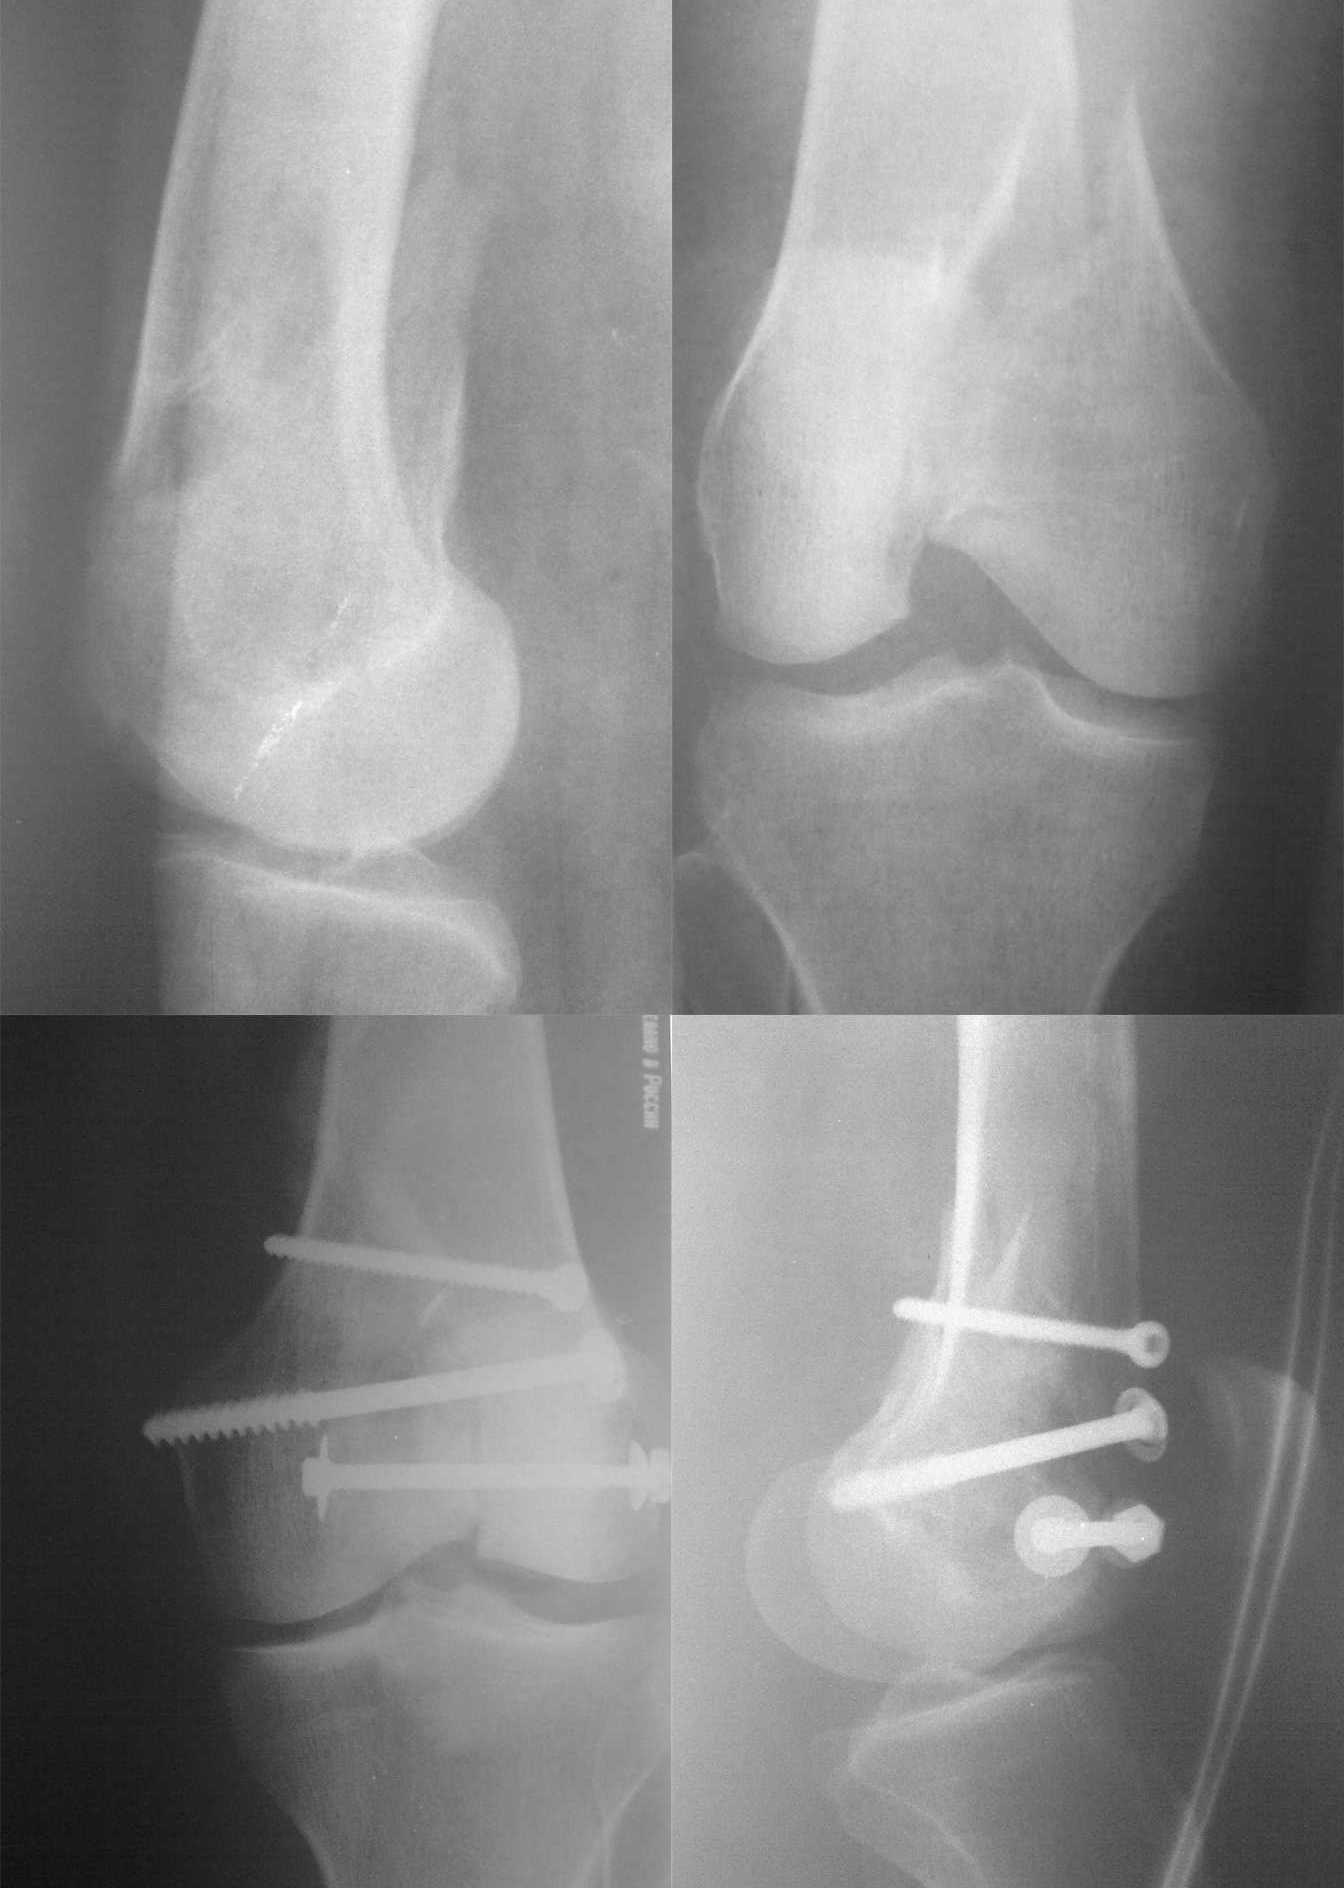

Уважаемые коллеги выскажите пожалуйста ваше мнение по поводу остеосинтеза свежего

перелома внутреннего мыщелка бедра